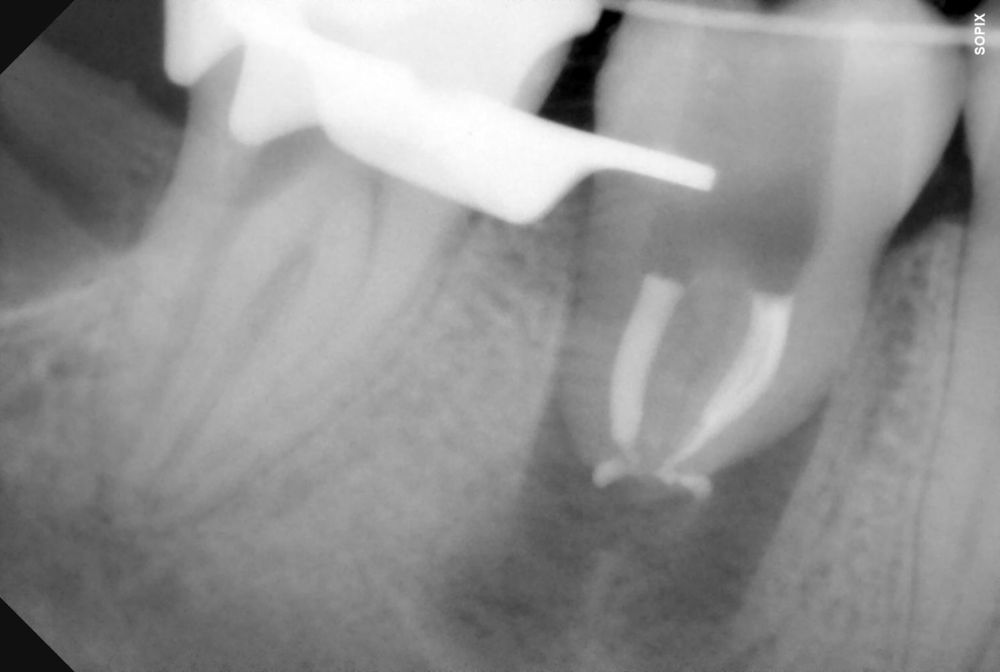

El autotrasplante dental es una opción terapéutica para aquellos casos en la que una pérdida dentaria es reemplazada por un diente donante del mismo paciente. Este autotransplante colocado en el alveolo puede ser inmediato o diferido. Suele estar indicado en paciente joven, siendo más frecuente el autotransplante de cordal a primer o segundo molar, y el de premolar a incisivo. El diente donante debe reunir unos criterios clínicos que aumenten el éxito de la técnica, basados en la morfología, el estadio de desarrollo radicular y la salud periodontal. La planificación se llevará a cabo con un CBCT y simulación virtual que genere un prototipo réplica en 3D; esto permite evaluar las dimensiones del diente donante para su correcta colocación en el alveolo receptor.

Se reporta el caso de un autotrasplante del tercer molar inferior derecho al alveolo postextracción de un primer molar inferior, en una paciente de 22 años de edad. Actualmente, el autotransplante se considera una opción de tratamiento si se siguen los criterios de selección del caso adecuados, y se realiza una técnica quirúrgica protocolizada. El diagnóstico planificado mediante CBCT, la simulación virtual y la confección de una réplica en 3D optimiza la técnica de forma segura, predecible con tiempos de cirugía menores.

El sitio receptor debe garantizar la adaptación del diente donante, se realizará un diagnóstico mediante planificación con CBCT que permita segmentar virtualmente el diente donante y llevarlo digitalmente al sitio receptor3.

La confección de la réplica 3D del diente se ha de realizar con material biocompatible y esterilizable mediante radiación gamma y beta. La ventaja del modelo estereolitográfico es minimizar el tiempo extraoral del diente donante, el daño al ligamento periodontal, así como poder remodelar el alveolo receptor sin usar el diente donante5,13,14.